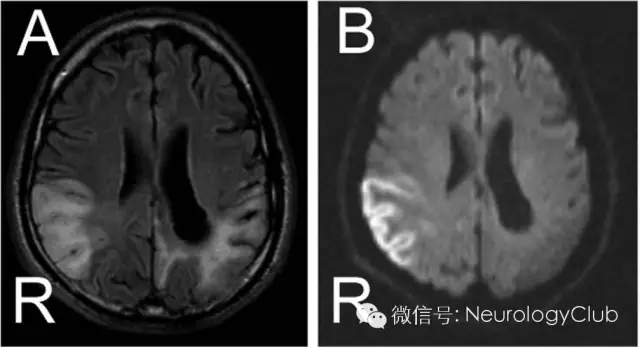

(图1:A:FLAIR;B:DWI)

MRI黑水像(图1A)可见双侧顶枕区不对称的异常高信号。相应的DWI(图1B)上可见病灶弥散受限,而ADC呈低信号(图未放),提示右侧顶枕区急性梗死,而左侧顶枕区应为先前梗死病灶。锝-99m SPECT灌注扫描可见左侧顶枕区灌注缺损(图2)。